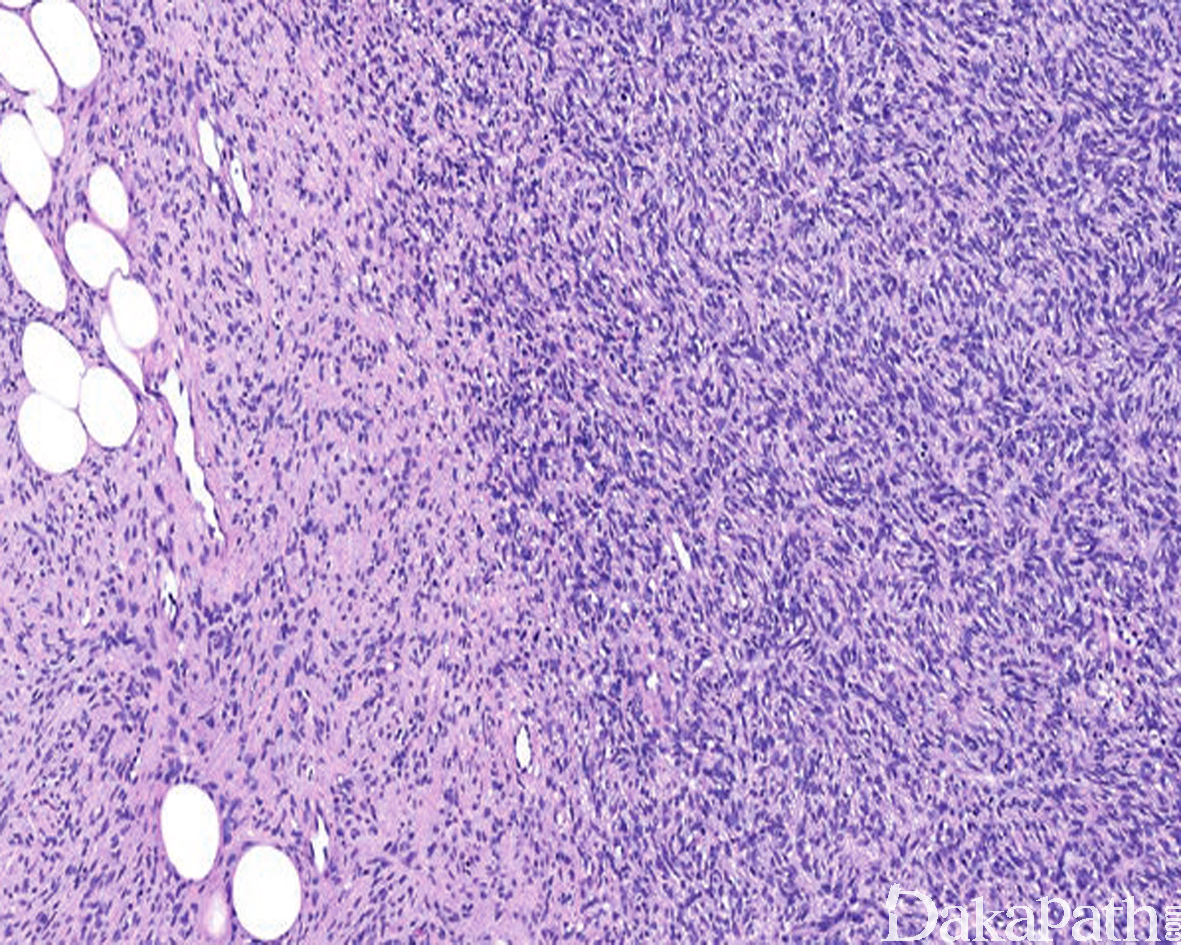

一种发生于皮肤的低度恶性纤维母细胞性肿瘤,组织学上由单型性的梭形细胞呈致密的席纹状结构组成,伴蜂窝状浸润皮下脂肪组织。

肿瘤主要位于真皮层,弥漫浸润性生长,浸润脂肪组织形成特征性的蜂窝状或蕾丝样 (或称花边样)浸润图像;

瘤细胞均匀较一致,呈两端细长的纤维母细胞样,呈一致的致密的席纹状排列,少数病例内可见局灶的血管外皮瘤样排列;

瘤细胞常紧密围绕残留的汗管等皮肤附件组织;